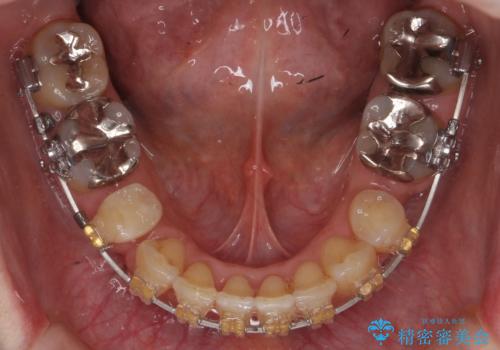

- 審美装置

- 3年3ヶ月

- 10-30回

叢生も著しく、少し年齢が上がってからの矯正治療となり、結果ブラックトライアングルが出てしまいましたが、並びの改善で非常に満足していただけました。